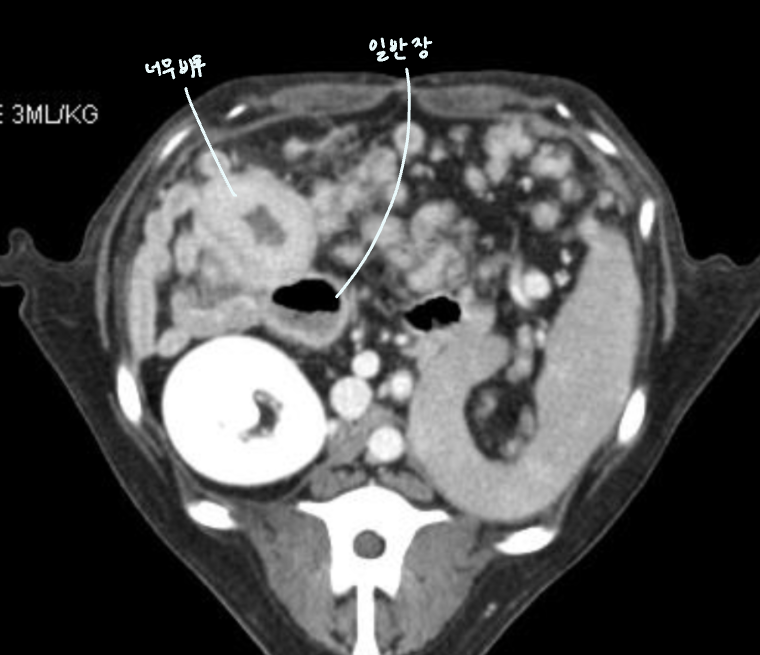

| Musclaris thickening of small intestine | DDx) |

![]() | 1. Lymphoma (early stage ๊ฐ๋ฅ์ฑ) 2. IBD 3. Reactive lymphadenopathy |